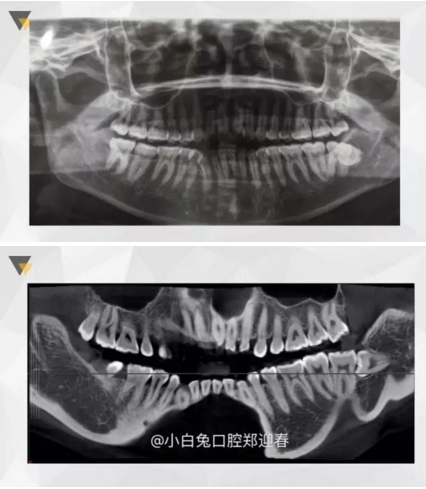

3.png

有路你不走,非要往前擠!

4.png

本是同兄弟,相煎何太急!